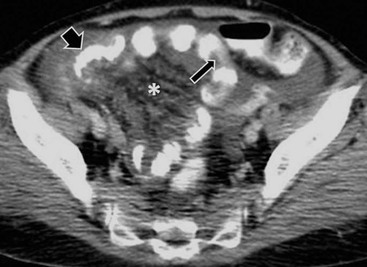

Peritoneal seeding is a common mechanism of metastatic dissemination in advanced gastrointestinal and gynaecological malignancies. Peritoneal carcinomatosis (PC) is the term given to malignant tumour seeding of the peritoneum with most common primaries being the ovarian (71%), gastric (17%) and colorectal (10%) cancers. When cancer cells from a growing primary neoplasm reach the peritoneal surface, they are carried out by the peritoneal fluid and disseminated throughout the peritoneal cavity. Distribution of disease in PC is related to peritoneal fluid circulation along predetermined anatomical routes as previously described in the section ‘Ascites’. This peritoneal fluid circulation and the areas of temporal stasis of fluid explain the distribution of peritoneal seeding. Pooling of ascites favours the deposition and growth of seeded malignant cells. The most common seeding sites include the pouch of Douglas, the distal small-bowel mesentery near the ileocaecal junction, the sigmoid mesocolon, the right paracolic gutter, the pouch of Morison and the right subdiaphragmatic area.3 In general, more aggressive neoplasms exhibit malignant peritoneal deposits closer to the primary tumour, as opposed to less aggressive neoplasms that tend to manifest deposits in remote areas in the abdominal cavity. Variable amounts of ascites may accompany peritoneal seeding but ascites is not always present. Ascitic fluid is sometimes locculated and/or septated, and therefore it may be absent in dependent areas such as the pelvis. Peritoneal deposits (Fig. 30-18) may appear as thickening or enhancement of the peritoneum, nodules or plaques on the peritoneal surfaces, masses or merely stranding of the mesenteric fat.